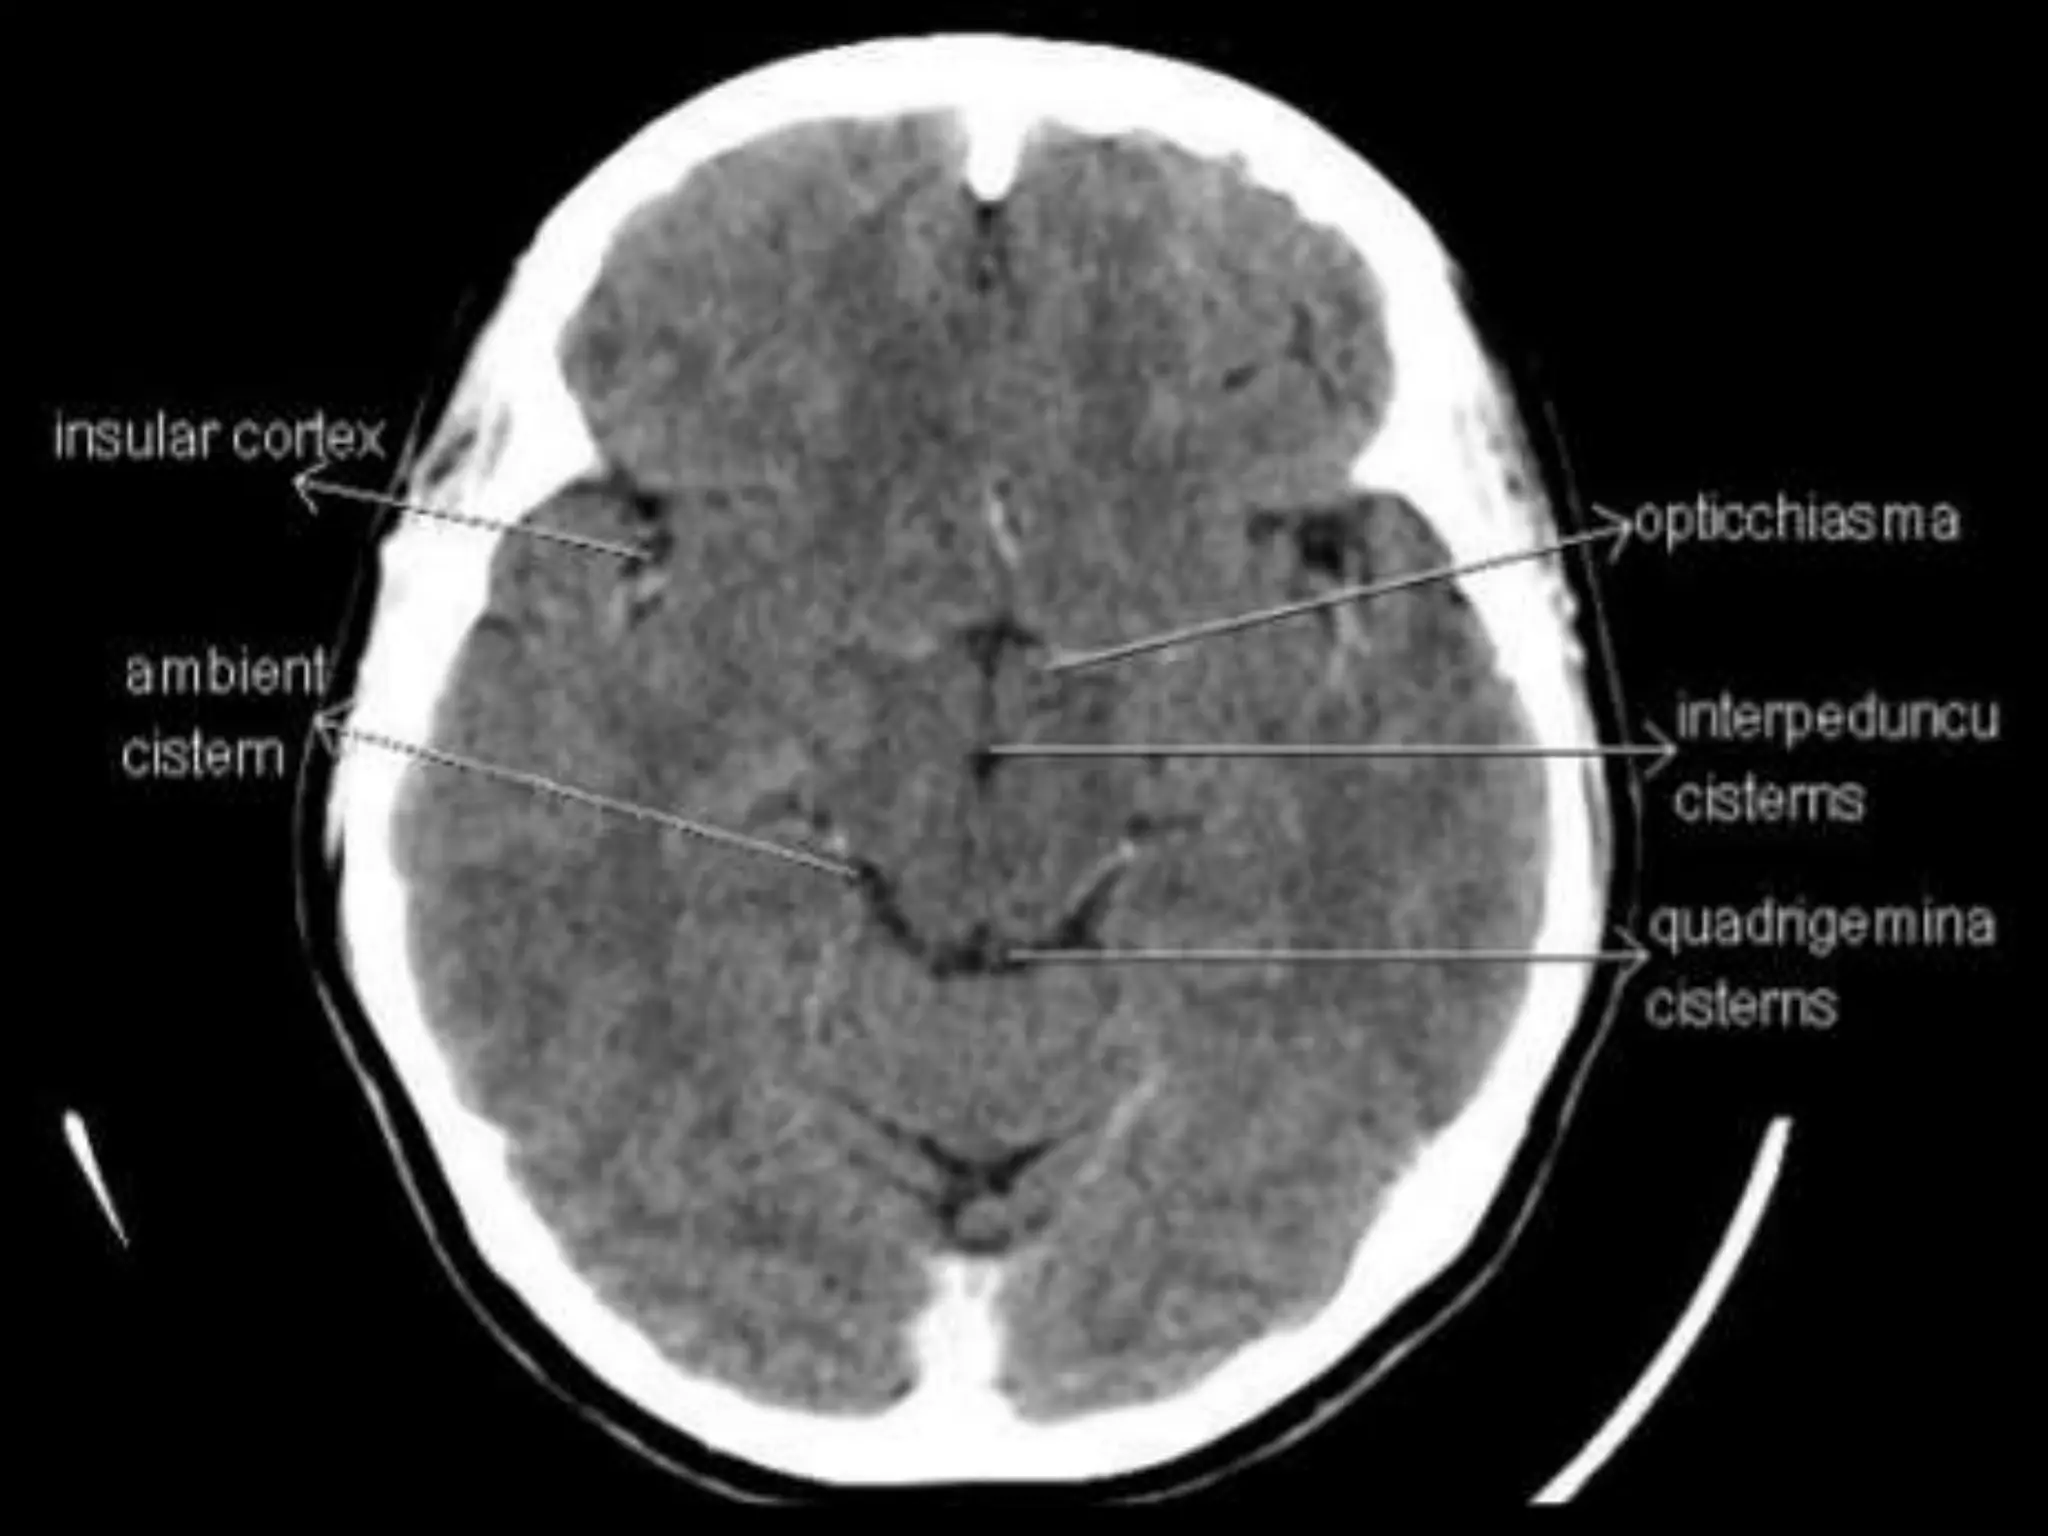

On CT and MR scans, the brain has been briefly viewed in

infratentorial and supratentorial sections, as described below.

CT scans are performed with a 15- to 20-degree angulation to

the canthomeatal line at 8-mm increments. MRI scans are

generally obtained parallel to the AC-PC line in the axial plane

Sectional Anatomy: NormalAxial CT and MRI Anatomy. On CT and MR scans, the brain has been briefly viewed in infratentorial and supratentorial sections, as described below. CT scans are performed with a 15- to 20-degree angulation to the canthomeatal line at 8-mm increments. MRI scans are generally obtained parallel to the AC-PC line in the axial plane with 6-mm slice thickness. Using the sagittal view, the coronal sections are acquired parallel to the brain stem, and the sagittal sections are obtained perpendicular to the axial section. On MRI studies, cranial nerves IX and X can be demonstrated at this level because they emerge from the postolivary sulcus. The posterior aspect of the cerebellar hemispheres is outlined by the inferior portion of the cisterna magna.